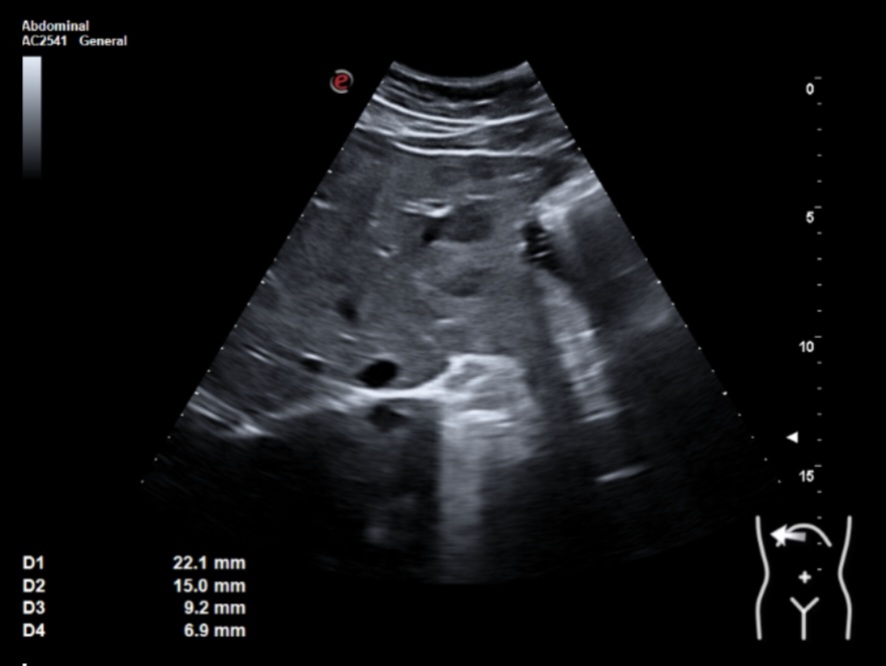

Ecografía clínica: múltiples lesiones en parénquima hepático bien delimitadas de hasta 2 cm, hipoecogénicas, en ambos lóbulos. Tamaño normal del hígado (15 cm) pero bordes obtusos. Vía biliar no dilatada. Vesícula alitiásica. Porta de calibre normal. Área pancreática no visualizada por gas intestinal. Ambos riñones normales. Vejiga vacía, no valorable.